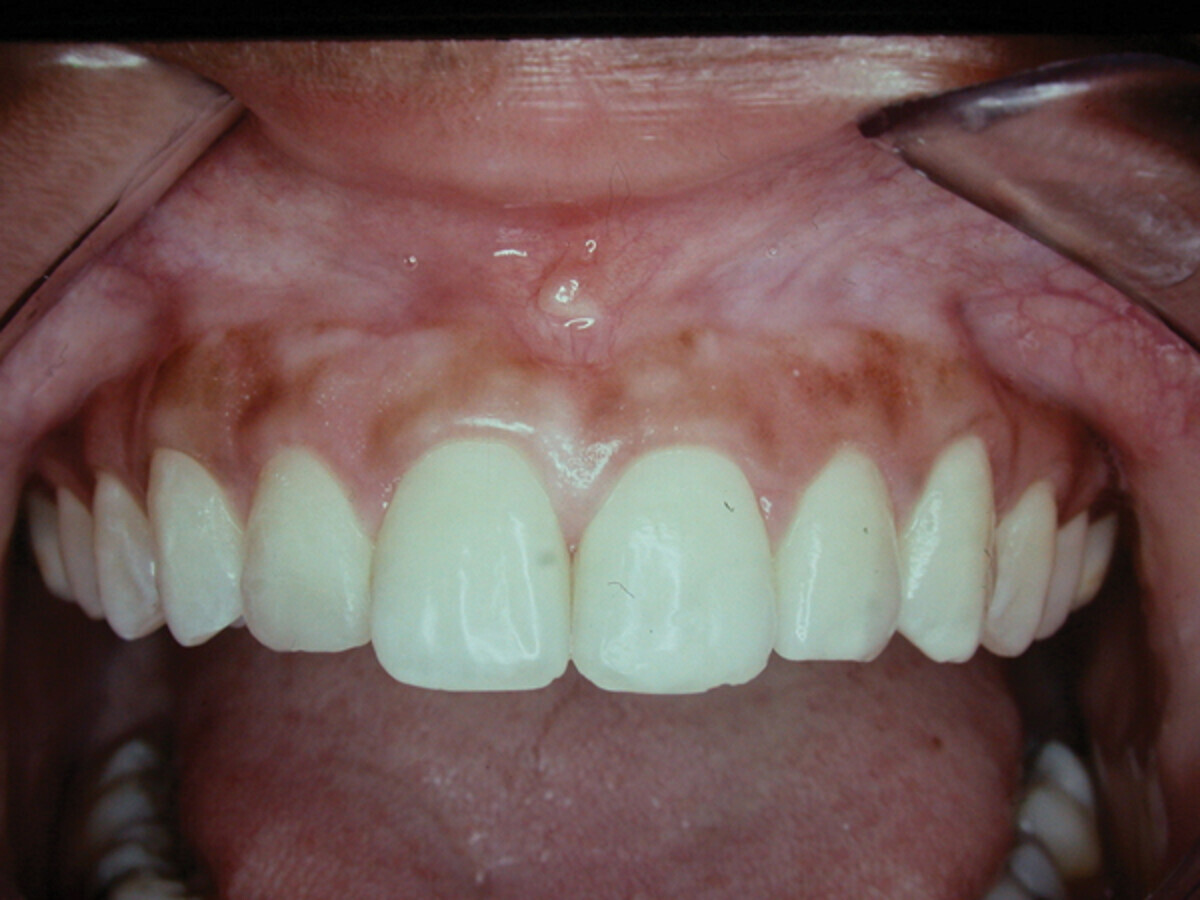

Fig. 3: Healed periodontia. Enamel exposure full and natural. Tooth #7 restored. (Photo: Dr. David L. Hoexter)

Fig. 4: Patient loves and is motivated to care for her new, bright, symmetrical smile. (Photo: Dr. David L. Hoexter)

The tissue was now placed at the desired level, usually at the symmetrical cervical height. Using the cuspid cervical height, in this case, the laterals and the centrals were positioned and sutured with a sling suture technique (Fig. 2) at the desired symmetrical level. Notice that the natural length of the incisors are exposed, but not the roots. The interproximal tissue is maintained to avoid the previously mentioned black-diamond appearing spaces that result when the interproximal tissues are removed. Notice the now exposed full enamel covering of the teeth involved, giving the length of the teeth the exposure required for the goal of “that smile” (Fig. 3). After the final stage, the young woman was ecstatic about her new bright smile. Her #7 was restored with a composite restoration. She maintains her oral health enthusiastically with oral hygiene, keeping the now healthy anterior periodontia maintained. The homogeneous color of the gingiva is symmetrical in lateral and vertical dimensions. There are no dark spaces interproximal, and the cervical symmetry of the teeth aid her ability to enjoy her glowing smile. The previously square-appearing teeth, are now restored to a natural, longer-appearing crown length, with the cervical gingiva on an even, lateral-linear appearance.